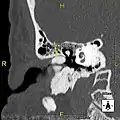

Exostosis in ear canal